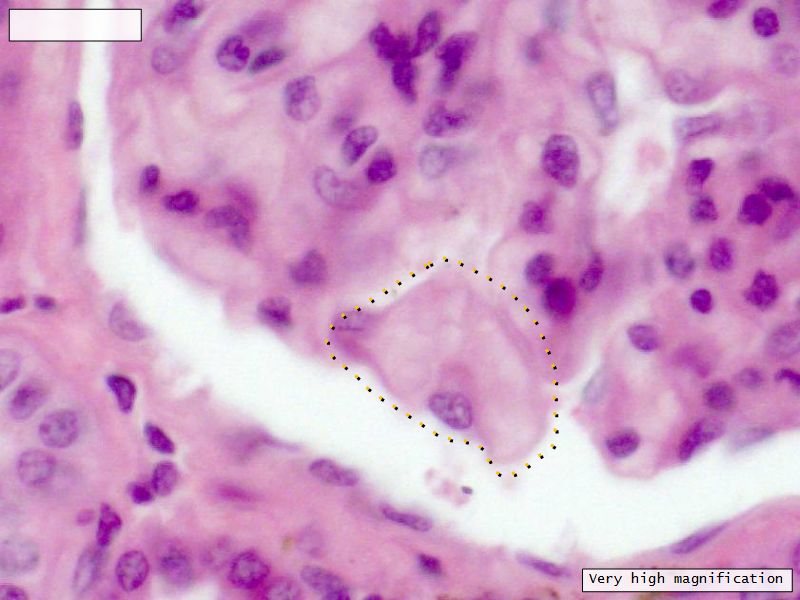

Epithelium layers

• Capillary endothelium

• Visceral layer of epithelium

• Podocytes

• Resting on glomerular basement membrane

• Capsular space

• Parietal layer of epithelium

• Simple squamous epithelium

Glomerular filtration barrier

• Three layers

• Fenestrated epithelium

• Exclude blood cells & platelets

• Glomerular basement membrane

• Main filtration barrier

• Thick

• Fused epithelial & endothelial BM

• Replenished by podocytes due to removal by mesangial cells

• Glomerular epithelium

• Through filtration slit

Podocytes

• Protrude into capsular space

• Attached to basement membrane

• Long cytoplasmic extensions

• Primary processes

• Secondary processes

• Podocyte feet

• Tightly spaced

• Filtration slits 20 - 30 nm wide